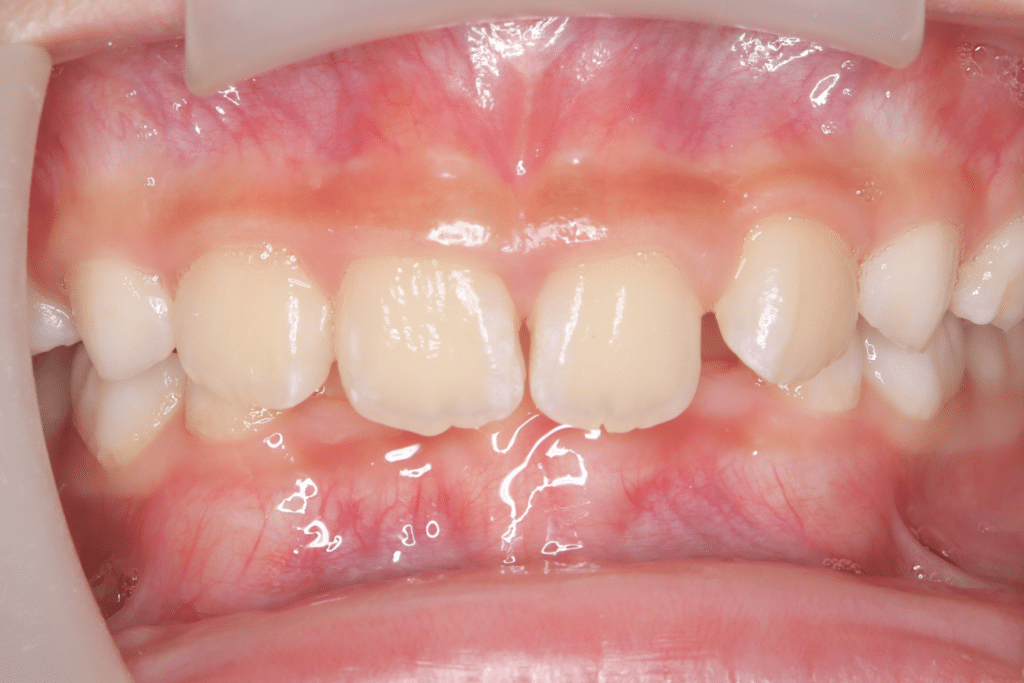

過蓋咬合

(9歳4ヶ月)

開始後2ヶ月

(開始後2ヶ月目)このあたりからマウスピース使用時間は起きてる時60分が可能となった